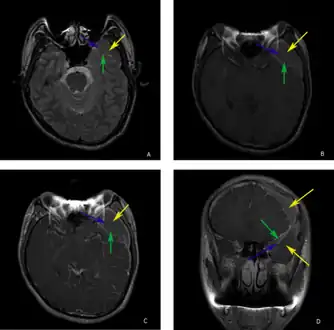

A CT scan of an arachnoid cyst

The diagnostic process typically begins with a medical history workup followed by a medical examination by a physician. Imaging tests, such as CT scans and MRIs, help provide a clearer picture. The physician typically looks for fluid (or other bodily substance) filled sacs to appear in the scans, as is shown in the CT scan of a colloid cyst. A primary health care provider will refer an individual to a neurologist or neurosurgeon for further examination. Other diagnostic methods include radiological examinations and macroscopic examinations. After a diagnosis has been made, immunohistochemistry may be used to differentiate between epithelial cysts and arachnoid cysts.[2] These examinations are useful to get a general idea of possible treatment options, but can be unsatisfactory to diagnose CNS cysts.[3][5] Professionals still do not fully understand how cysts form; however, analyzing the walls of different cyst types, using electron microscopes and light microscopes, has proven to be the best diagnostic tool. This has led to more accurate cyst classification and correct course of action for treatments that are cyst specific. In the past, before imaging scans or tests were available, medical professionals could only diagnose cysts via exploratory surgery.[2]